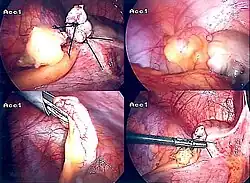

Appendicectomia laparoscopica

Introdotto nel 1983, l'appendicectomia laparoscopica è diventata un intervento sempre più diffuso per risolvere l'appendicite acuta.[57] Questa procedura chirurgica consiste nel praticare, da tre a quattro, incisioni nell'addome, ciascuna della lunghezza variabile dai 6,4 a 12,7 mm. Successivamente viene inserito uno speciale strumento chirurgico, chiamato laparoscopio, in una delle incisioni. Il laparoscopio è collegato a un monitor ed è progettato per aiutare il chirurgo a ispezionare l'area infetta nell'addome. Le altre due incisioni vengono utilizzare per la rimozione dell'appendice, grazie all'introduzione di strumenti chirurgici. La chirurgia laparoscopica richiede un'anestesia generale e può durare fino a due ore. L'appendicectomia laparoscopica presenta diversi vantaggi rispetto all'appendicectomia "a cielo aperto", tra cui un recupero post-operatorio più breve e meno doloroso e una minore percentuale di infezioni superficiali del sito chirurgico. Tuttavia, l'occorrenza di un ascesso intra-addominale è quasi tre volte più prevalente nell'appendicectomia laparoscopica rispetto all'appendicectomia aperta.[58]